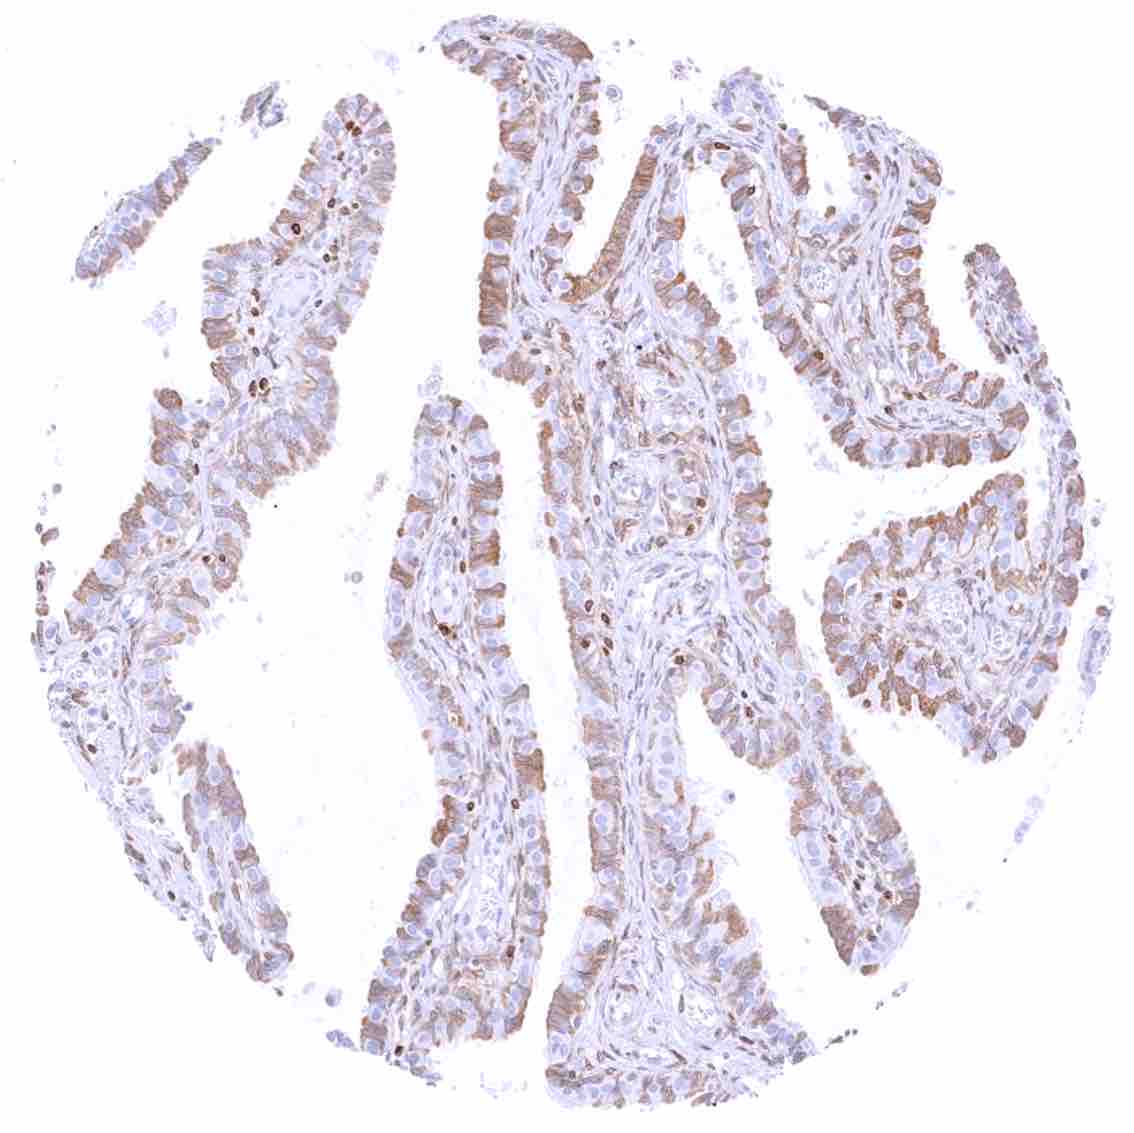

Fallopian tube, mucosa – Strong cytoplasmic bcl-2 staining of a subset of epithelial cells.